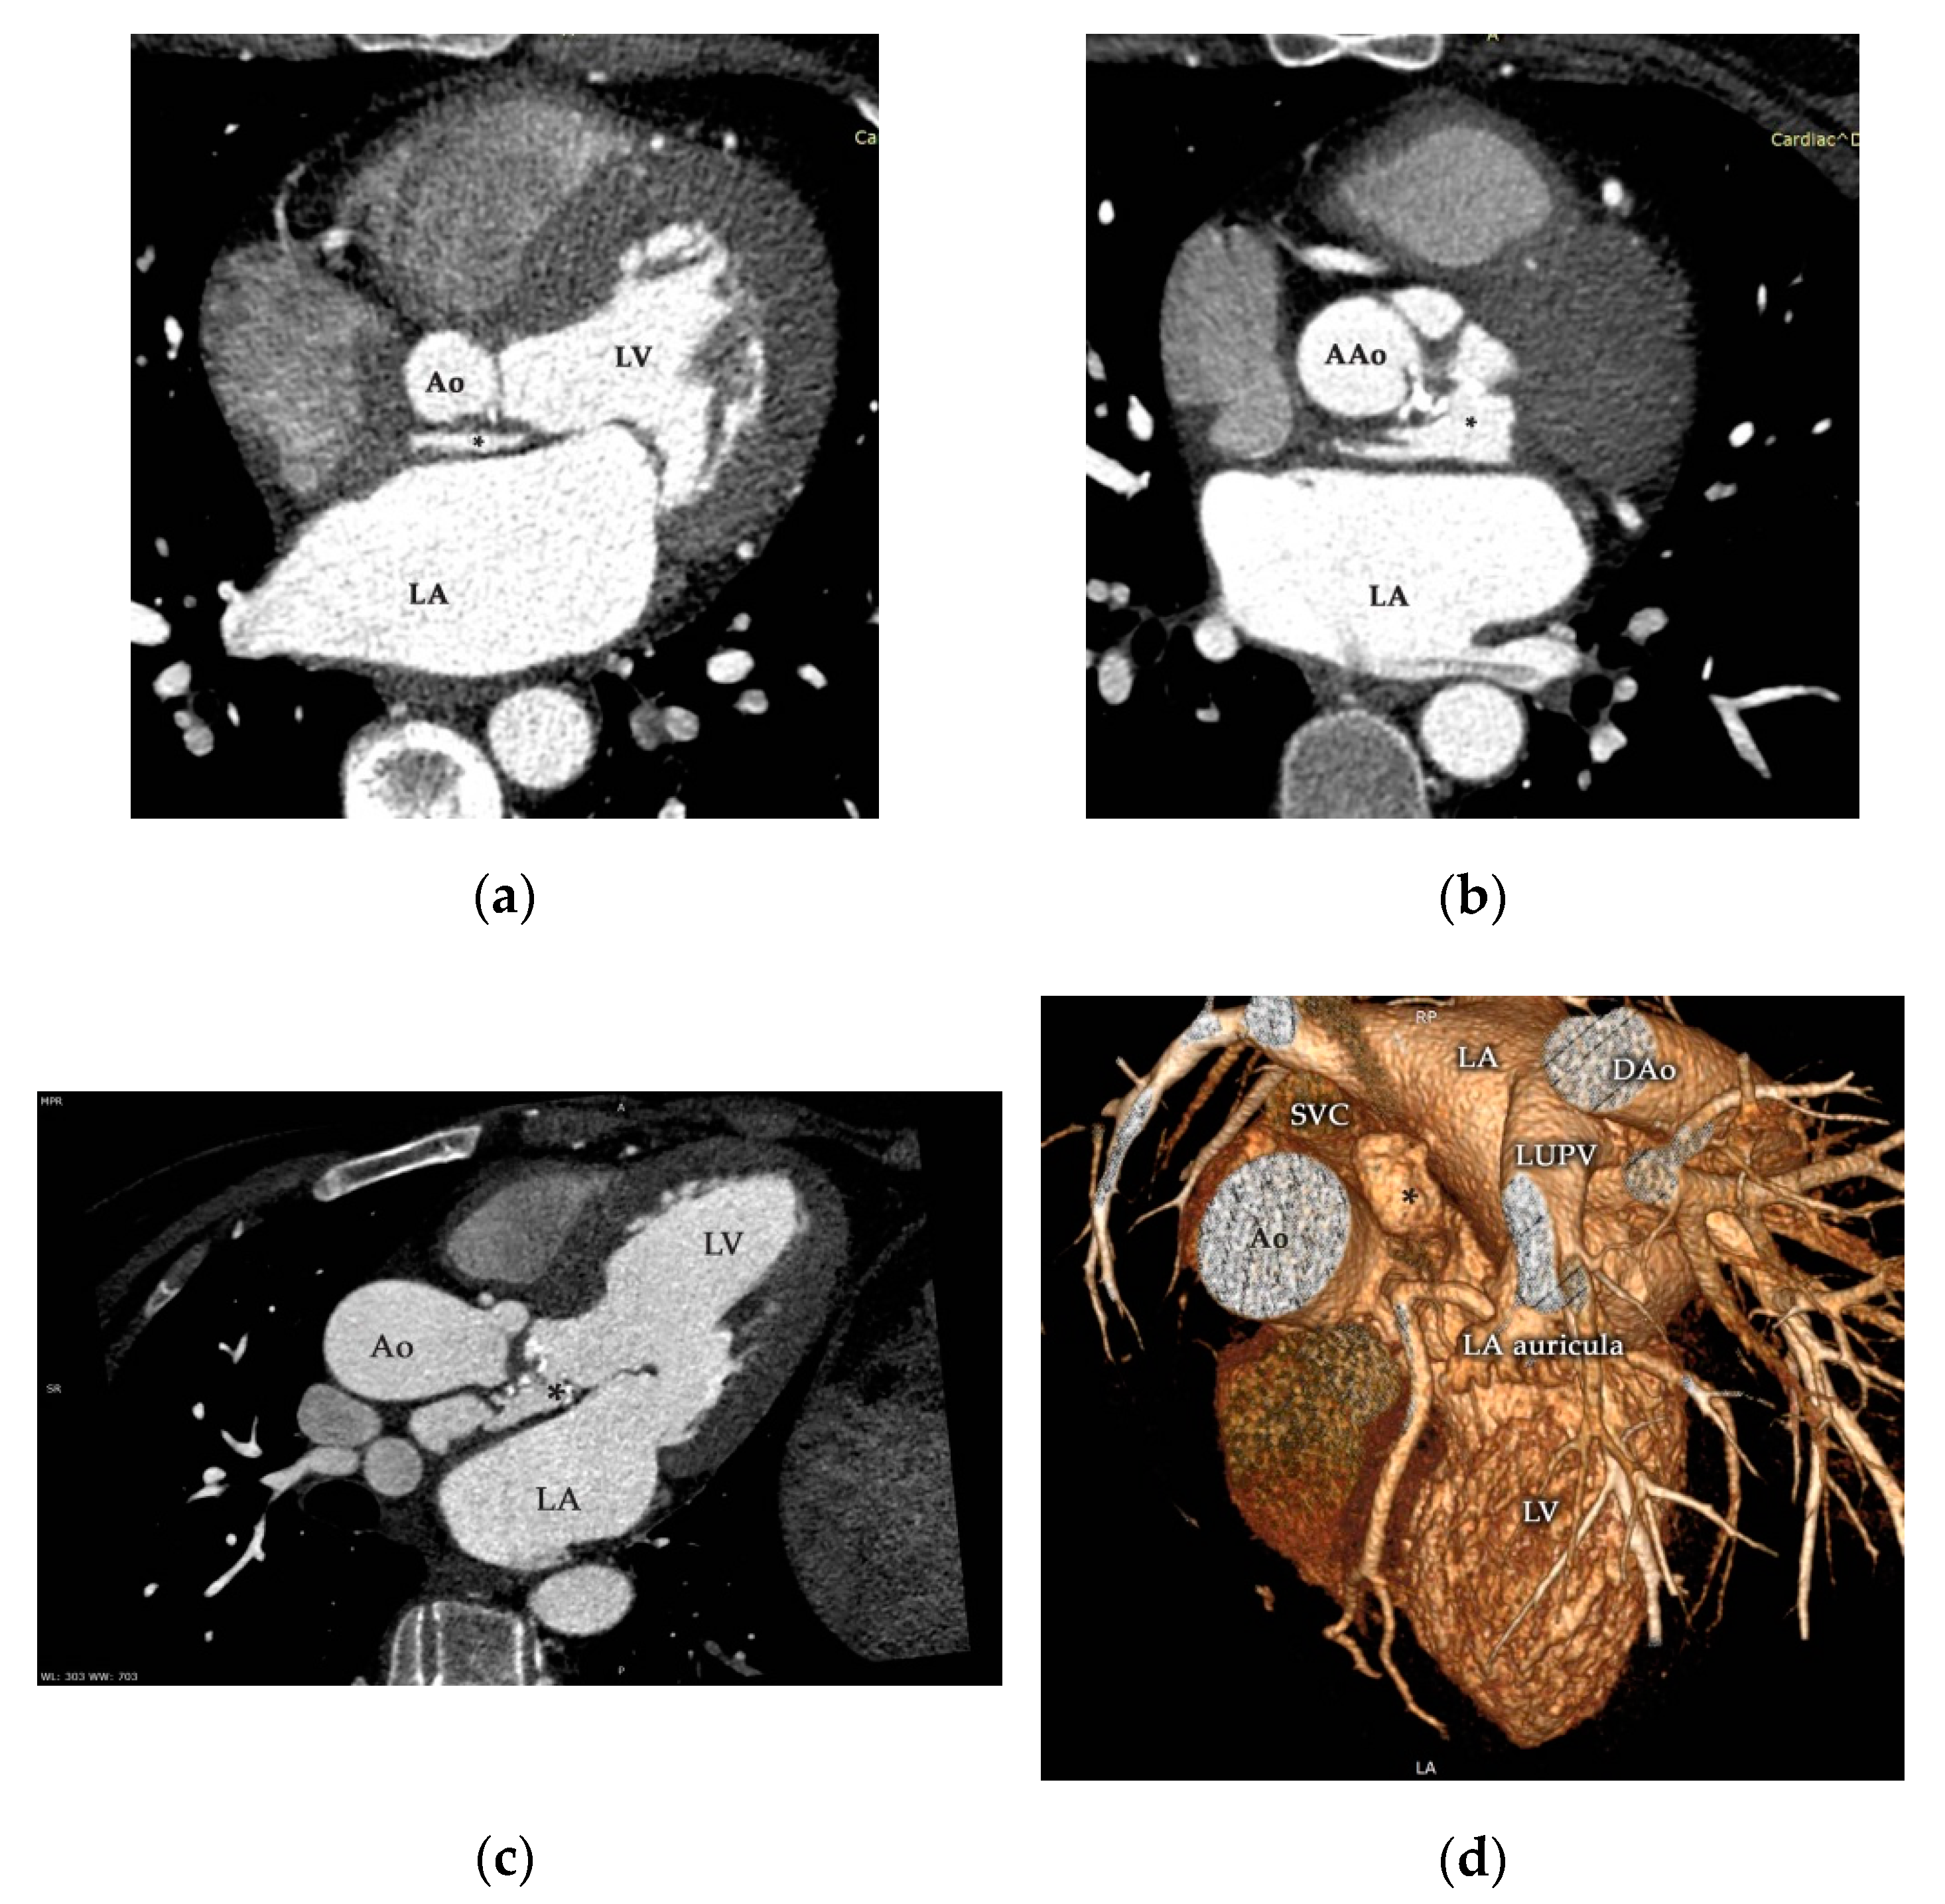

Contrast-enhanced ECG-gated multidetector-row cardiac computed tomography (MDCT; Somatom Definition Flash™, Siemens Healthcare GmbH, Erlangen, Germany) corroborated the aforementioned presence of a giant pseudoaneurysm originating in the LVOT at the level of the mitral and aortic intervalvular fibrous fascia extending cranially between the right pulmonary artery and the anterior caudal of the left atrium (Figure 5, Supplementary Movie S3). Coronary arteries were normal, with no signs of compression and the absolute coronary artery calcium score (Agatston method) was zero.

Figure 5.

Contrast-enhanced ECG-gated multidetector-row cardiac computed tomography (MDCT) study of the aortic valve and ascending aorta during the cardiac cycle corroborated the presence of P-MAIVF (*) with the appearance of contrast media (a–c). Three-dimensional reconstruction (d) supported the aforementioned findings, and precise localization is clearly demonstrated. Ao—aorta, AAo—ascending aorta, DAo—descending aorta, LA—left atrium, LUPV—left upper pulmonary vein, LV—left ventricle, SVC—superior vena cava.